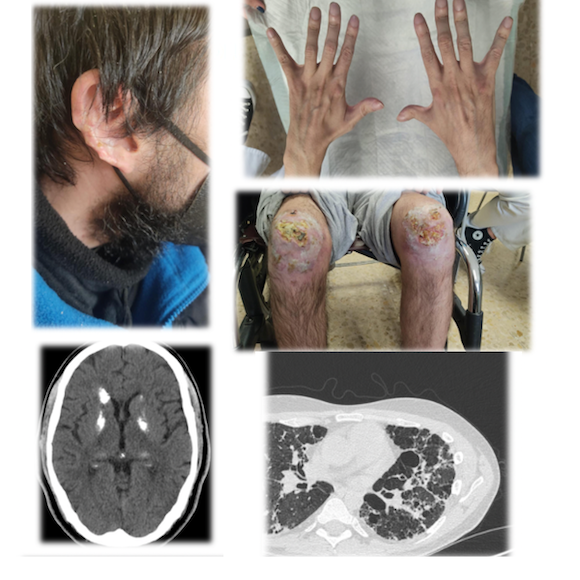

Es derivado en 2001, a la edad de 17 años, a consultas de Reumatología por clínica de poliartralgias de ritmo inflamatorio de un año de evolución en ambas manos, rodillas y pies, lesiones pruriginosas eritematoso-violáceas en dedos, pies, nariz y oreja con empeoramiento en los meses de invierno acompañado de Raynaud trifásico y pérdida de tejido celular subcutáneo en ambos pabellones auriculares, siendo valorado por dermatología, con sospecha de perniosis/sabañón, sugestivo de lesiones chilblain lupus erythematosus- like, sin poder realizar biopsia cutánea para diagnóstico confirmatorio, ante negativa del paciente. Además, refería disnea de moderados-grandes esfuerzos de meses de evolución con progresión en las últimas semanas y cefalea frontal intensa en el último mes, acompañado de aura visual, sonofobia y fotobia.

Radiografía de tórax con afectación intersticial en lóbulos inferiores y pruebas de función respiratoria compatible con patrón restrictivo. Se completa estudio con una broncoscopia transbronquial con hallazgos de fibrosis pulmonar con escasos macrófagos, junto con imágenes en TCAR compatible con patrón tipo NIU. Así mismo, ante clínica de cefalea, se solicitó un TC craneal con imágenes inespecíficas en sustancia blanca, sugestivas de calcificaciones de los ganglios de la base.

En resumen, se presenta un varón de 17 años con clínica de poliartritis erosiva FR positivo (título bajo), ANA+ y Anti-DNA+, linfopenia intermitente y una sola determinación ACA IgM positiva, lesiones cutáneas tipo perniosis/sabañón (chilblain lupus-like) y afectación pulmonar intersticial patrón tipo NIU junto con historia desde la infancia de infecciones recurrentes respiratorias, retraso de crecimiento ponderal y estado inflamatorio persistente. Iniciando tratamiento con hidroxicloroquina, prednisona a dosis medias y azatioprina, con empeoramiento articular, pulmonar y cutáneo en revisiones sucesivas. Años más tarde, se objetiva la aparición de extensas lesiones necróticas en ambas rodillas, con biopsia cutánea inespecífica e IFD negativa, sin datos de trombosis, infiltrados linfocíticos o datos de vasculitis.

- TAC tórax de alta resolución: afectación intersticial difusa, mayor en língula, LII, LMD. Pequeñas áreas de panalización en LII. Patrón NIU.

- TC craneal: lesiones inespecíficas en sustancia blanca, sugestivas de calcificaciones de ganglios de la base.